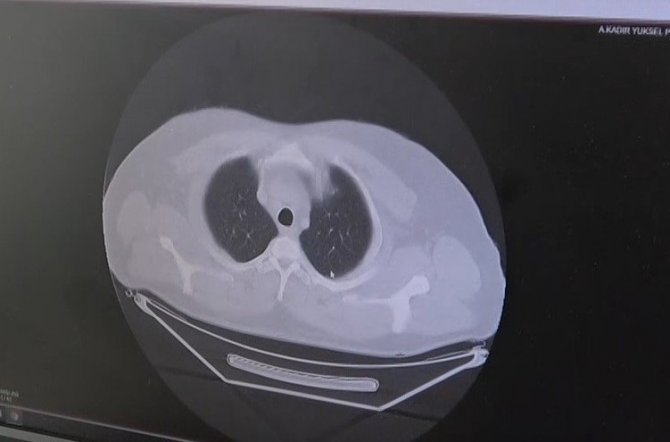

Korona virüsün bulaşmasından sonra 3 gün içinde hızla akciğere nasıl yayıldığını gösteren grafikleri gösteren Dr. Demir, hastanede yoğun bakımda yatış yapanların çoğunluğunun delta varyantı olduğunu söyledi.